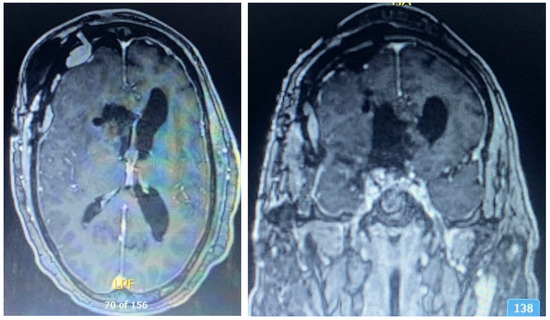

2.1. Case 1